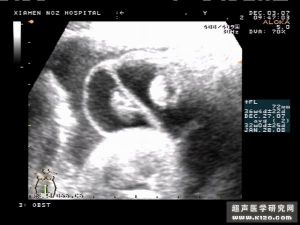

幼兒精索

胎兒雙側睪丸鞘膜積液聲像圖 出生後從內環至睪丸方整段精索部分的鞘突逐漸萎縮切台。睪丸部分的鞘突形成囊狀睪丸固有鞘膜,正常的鞘膜腔內僅有少量漿液,當鞘膜的分泌和吸收功能失去平衡時,可引起期膜積液。鞘突在不同部位閉合不全,又可形成各種類型四鞘膜積液。

鞘膜積液分為四個類型:睪丸鞘膜積液,精索鞘膜積液,睪丸精索鞘膜積液和交通性鞘膜積液。其中睪丸鞘膜積液最為常見,其又可分為原發性和繼友性,後著由炎症、外傷、腫瘤、絲蟲病等引起。

睪丸鞘膜積液質軟,有彈性和囊性感,觸不到睪丸和附睪,透光試驗陽性。幼兒精索鞘膜積液它是一種常見疾病,可見於各種年齡。胎兒早期睪丸在腹膜後,7~9月時經腹股溝管下降進入陰囊,附著於睪丸的腹膜也隨之下降形成腹膜鞘突。